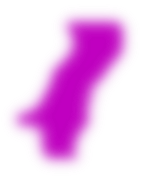

一个区域可以用不同的方式表示,例如作为二进制标签图(每个体素的值指定该体素是在区域内还是区域外)或闭合表面(表面网格定义区域的边界)。没有一种表示方式适用于所有情况:每种表示方式都有其优缺点,并根据需要使用。

| 二进制标签图 | 闭合表面 | 分数标签图 | 平面轮廓,带状 |

| 简单的2D查看和编辑, 总是有效(即使 变换或编辑后) | 简单的3D可视化 | 相当容易的2D查看 和编辑, 总是有效, 相当准确 | 准确的2D查看和编辑 |

| 不准确(有限的分辨率), 如果允许重叠则需要大量内存 | 难以编辑, 可能无效 (例如,自相交), 特别是在非线性 变换后 | 需要大量内存 | 在3D中模棱两可, 质量差 3D可视化 |